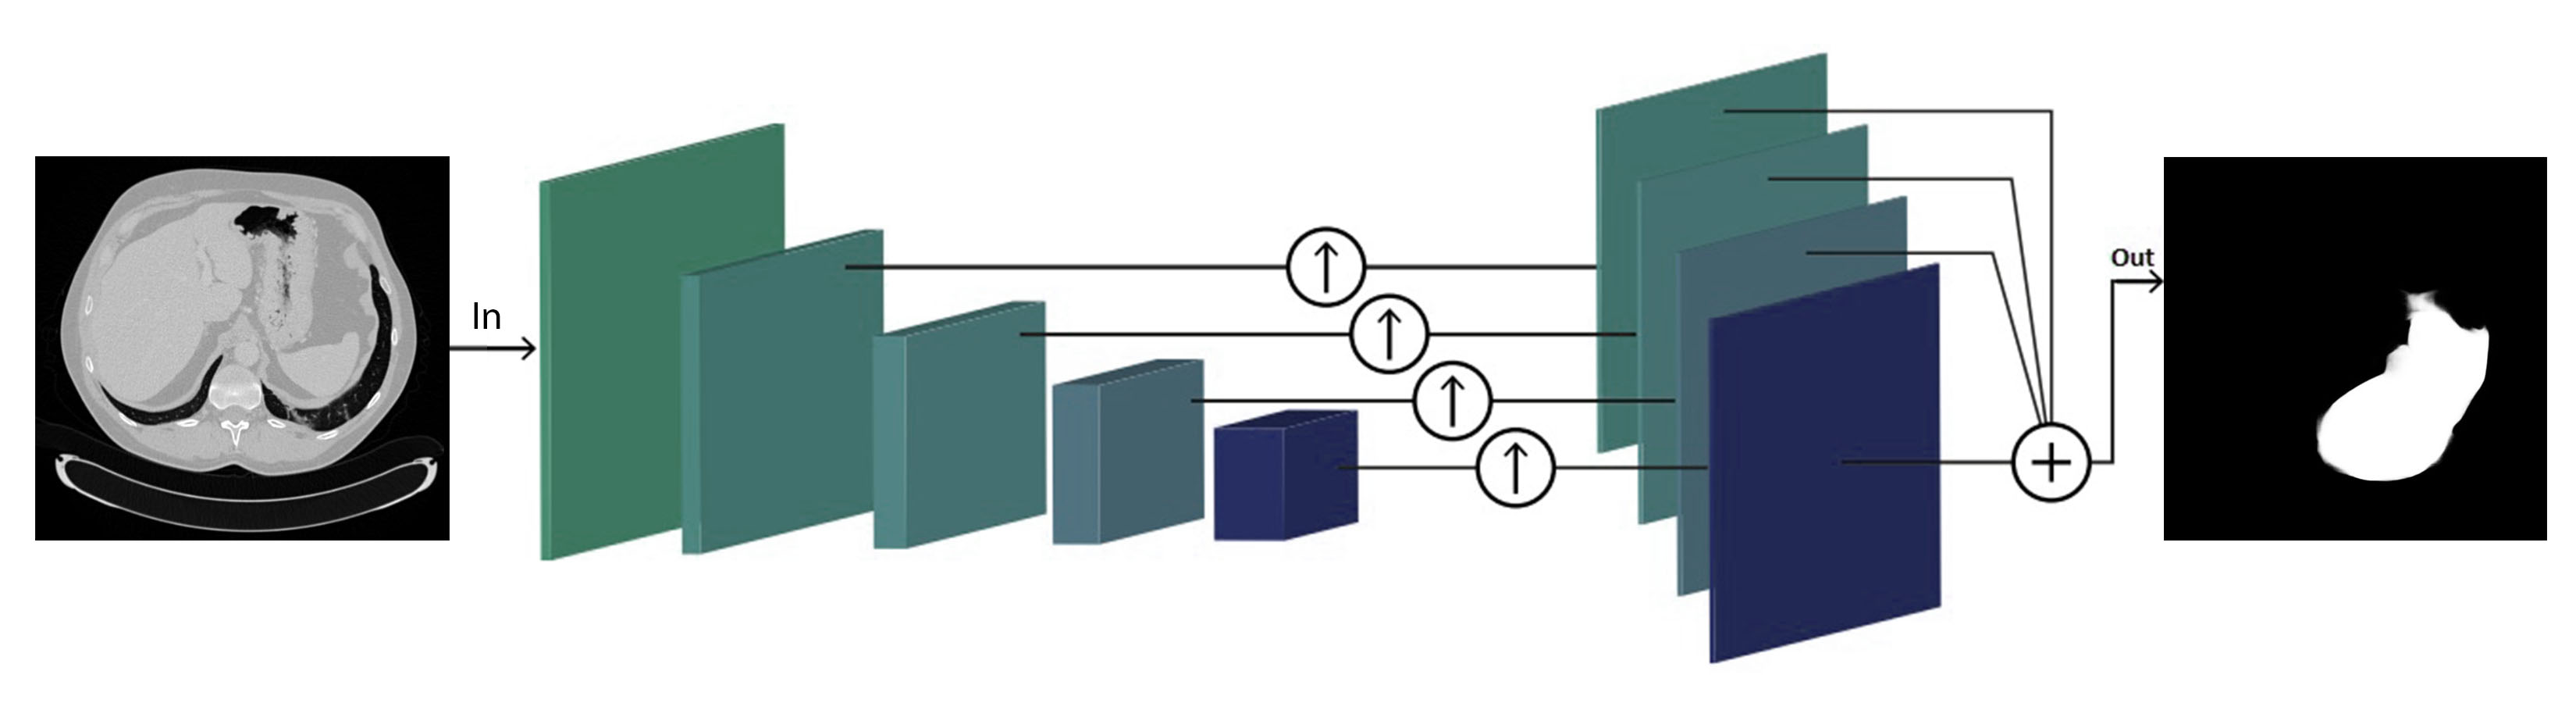

Being inspired from DRIU, the algorithm presented uses side outputs after each convolutional stage, all contributing to the final output. As the algorithm performs also lesion segmentation, the general architecture comprises multiple modules: liver segmentation, ROI cropping, lesion detector, lesion segmentation. An overview of the general architecture is presented in Figure 3.4, and a detail of the liver segmentation architecture is presented in Figure 3.5. The lesion segmentation architecture starts from the same architecture used for liver segmentation, with different added enhancements.

Originally the algorithm parsed the data as if the slices were independent, while in fact they have a strong 3D coherence. Also, the algorithm was pretrained with Imagenet, and it uses 3 channel images for training - RGB (Red, Green, Blue). Hence, as shown in Figure 3.6, the three channels can be fed simultaneously three slices of the volume analyzed, one at each RGB channel (2.5D approach), while during testing only the central output slice is kept. Figure 3.6 refers to the liver segmentation, but the approach is the same for the lesion segmentation network.